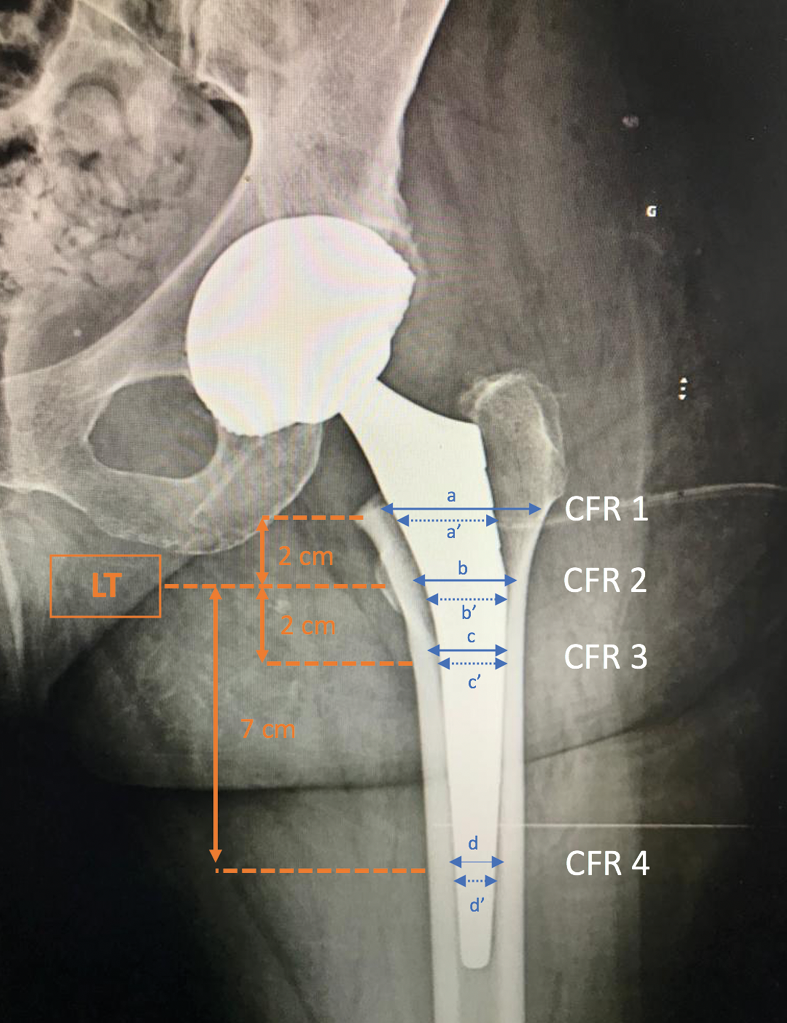

Implant size was determined using the canal fill ratio (CFR) [18] D’Ambrosio A, Peduzzi L, Roche O, Bothorel H, Saffarini M, Bonnomet F. Influence of femoral morphology and canal fill ratio on early radiological and clinical outcomes of uncemented total hip arthroplasty using a fully coated stem. Bone Jt Res. 2020 measured at four different points on the weight-bearing postoperative images: the lesser trochanter, 2cm above and below the lesser trochanter, and 7cm below the lesser trochanter (Figs. 1 & 2).